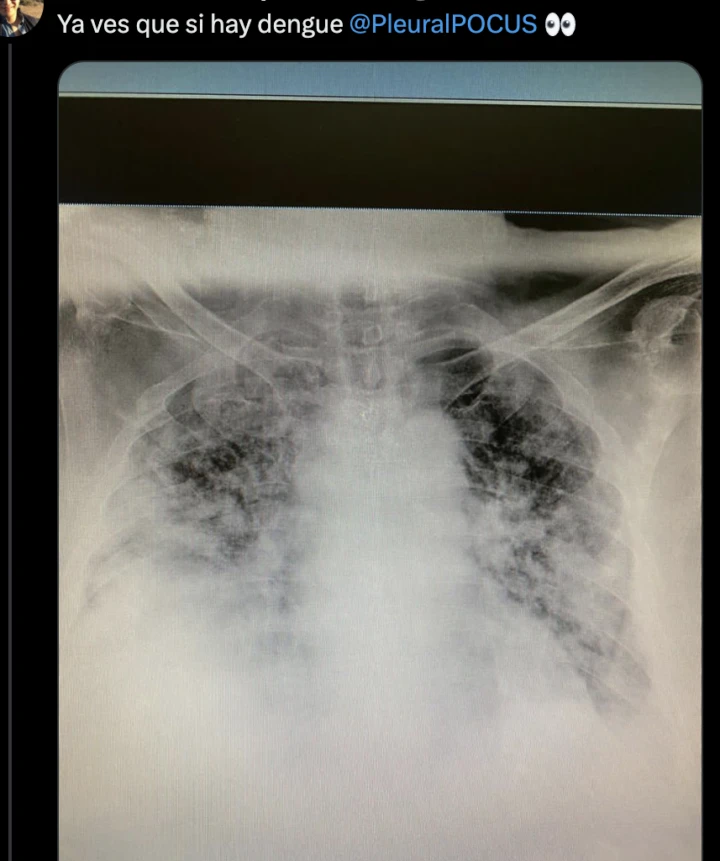

“Tuvimos algunas situaciones muy poco frecuentes. Uno de los ejemplos es un cuera que sufrió un síndrome de Guillain-Barré, que es una complicación descripta, pero muy rara. Sacando eso, no hemos registrado complicaciones no habituales. Lo que sí hemos tenido ahora, pero que no se relaciona con el dengue, son las neumonías atípicas y en formas bastante graves. No es un número muy alto, pero hemos tenido citacosis con mucha destrucción pulmonar”, informa.